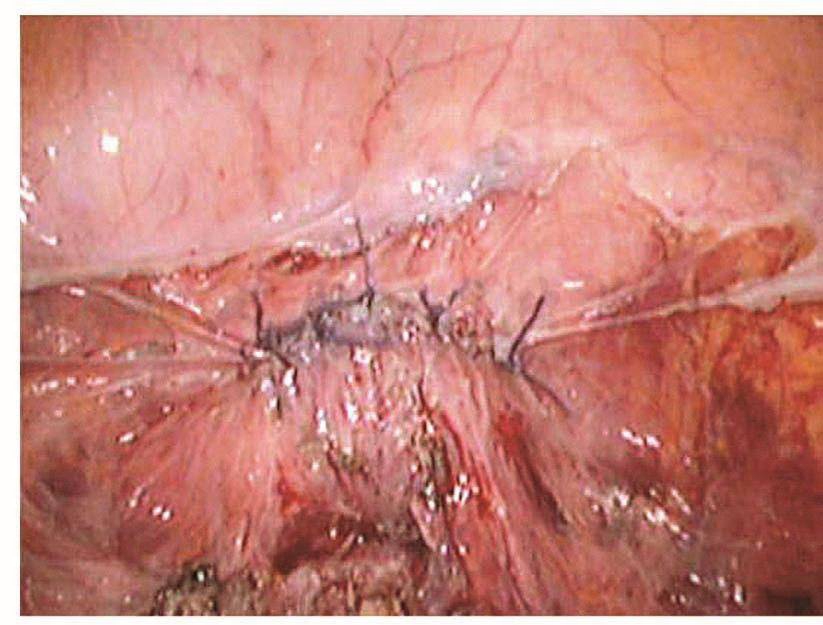

如果损伤长度>5mm,则需要手术处理。以往是先行暂时性肾盂造瘘下修补:根据笔者经验,如果术后15天内发现损伤,则可以直接采用腹腔镜下修补,可以减轻患者痛苦,缩短住院时间。该方法最关键的步骤是游离粘连的输尿管,因为,术后15天内组织开始出现明显的组织粘连。术前必须与患者及家属沟通并征得泌尿外科大夫同意后才进行手术。操作时,腹腔镜下探查盆腔,明确粘连程度及输尿管走向,分离粘连组织,暴露损伤的输尿管创面,从膀胱镜下插入导管,对合损伤面,用4-0的可吸收线在输尿管前、左、右三个方位各穿合一针。缝合时缝针从损伤口远端输尿管浆肌层进针,穿过黏膜层,再从近端黏膜层进针,穿出浆肌层,拉紧穿线,镜下打结。修补损伤面后,在膀胱镜下取出导管,再插入输尿管镜,明确输尿管通畅。然后,通过输尿管镜放进双J型支架,床边X线机明确双J管的位置,盆腔放置引流管,如果引流不多,48小时后取出。术后3个月在膀胱镜下取出双J管(图111~图116)。

图114 吻合输尿管

图115 修复后的输尿管